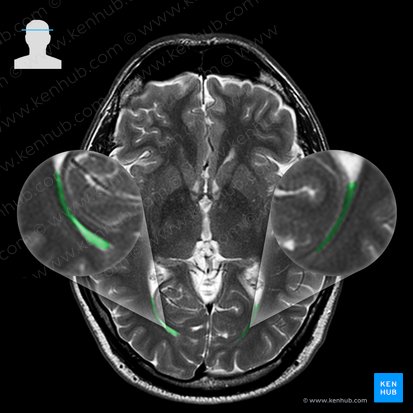

The hippocampal formation consists of the dentate gyrus, hippocampus and subiculum. On a coronal section, the hippocampal formation looks like a seahorse whose head begins with the dentate gyrus. On axial scans, it is the part of the temporal cortex that is immediately lateral to the pons. The dentate gyrus is found in the medial aspect of the temporal lobe. The dentate gyrus continues medially, deep into the temporal lobe, as the hippocampus proper. The hippocampus proper curves around the dentate gyrus, forming the floor of the temporal horn of the lateral ventricle. It then continues medially as the short subiculum. The subiculum courses medially and quickly continues as the parahippocampal gyrus. The parahippocampal gyrus curves inferiorly and emerges on the inferior surface of the brain.

The amygdala is a small almond shaped structure found superior and anterior to the temporal horn of the lateral ventricle. At the pons level, it is easily traceable as a circular structure found immediately anterior to the head of hippocampus.